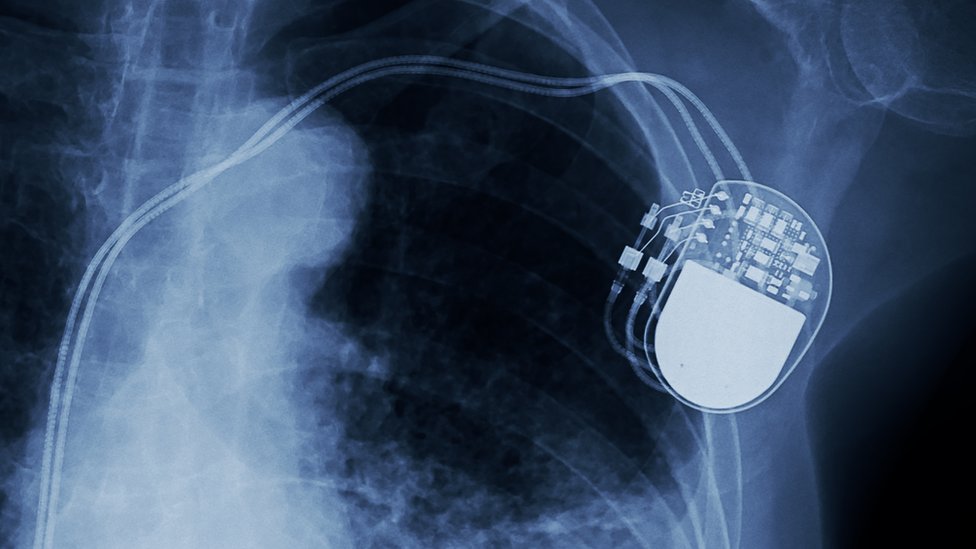

Mnogi često izjednačavaju bol u grudima sa srčanim udarom, ali postoji mnogo uzroka bola u grudima.